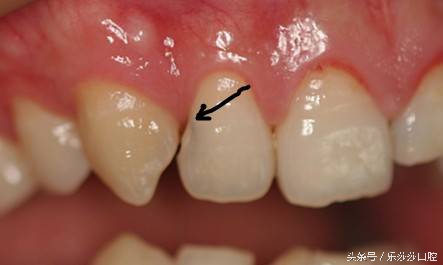

五、牙齿长得不齐

这种情况学名叫牙列不齐,牙齿排列「远近高低各不同」,比如牙齿的错位、扭转,自然更容易、更方便地让食物卡在这些地方,导致塞牙。